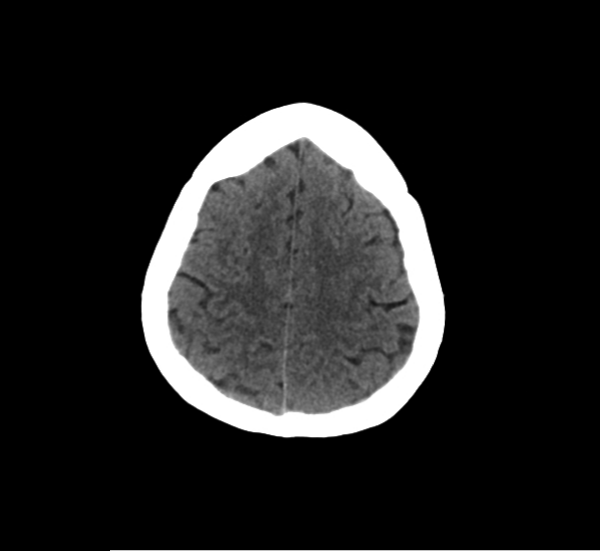

CT Brain Anatomy